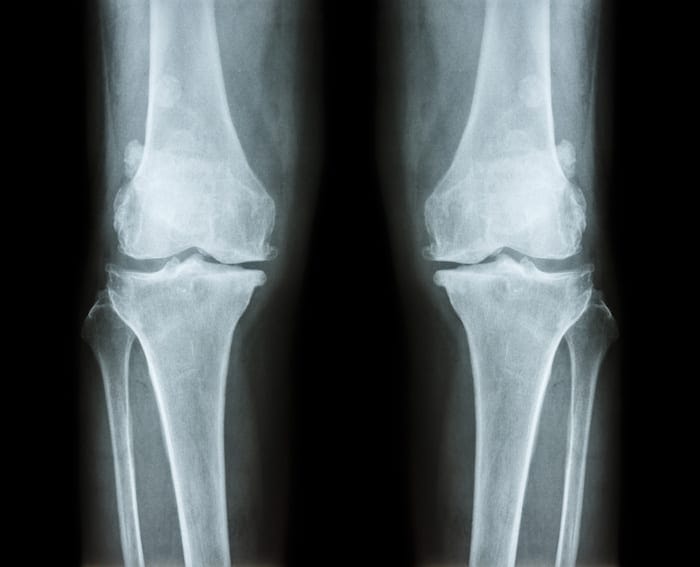

Do you feel some pain or stiffness when bending parts of your leg? If so, this may be a sign of a condition famously known as bone spurs, or osteophytes. Muscle cramps, weakness, or bumps beneath the skin are other signs that doctors usually use to diagnose bone spurs. In addition to bone joints (heels, knees, etc.), this condition may also manifest itself in the spine, which can be quite uncomfortable.

Fortunately, osteophytes may be managed or alleviated if the right procedures are applied; podiatrists have a lot of options when it comes to the treatment of bone spurs. This article aims to cover some common ways that bone specialists, like Eastern Idaho Foot Clinic, are using to help control this condition.